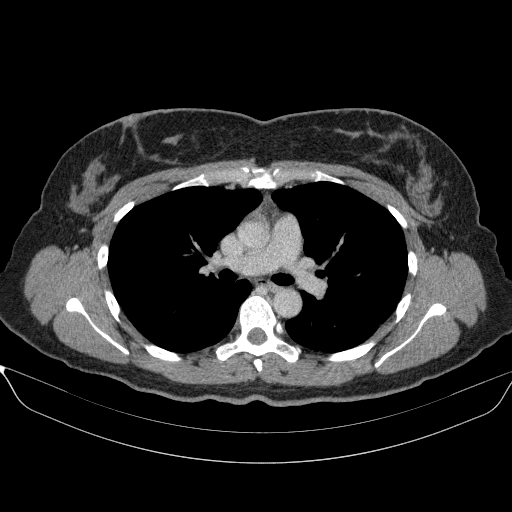

Slice 70 Targeting Evaluation

Slice: Slice_70

Slice Thickness: 1.5mm

Conversion: NATIVE β†’ VENOUS

Image Grid

4Γ—3 grid: Rows show different image types (Original NATIVE, Reconstructed NATIVE, Original VENOUS, Generated VENOUS), Columns show windowing techniques (No Window, Lung Window, Mediastinum Window)

Original NATIVE CT scan (input)

Full window (WL 1023.5, WW 4095 β†’ Low βˆ’1024, High +3071)

Original VENOUS CT scan

Generated VENOUS CT scan (A→B translation)